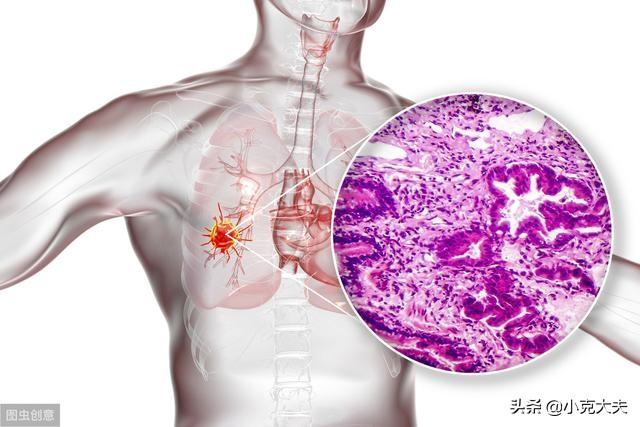

On ne saurait trop insister sur l'importance des poumons, mais le cancer du poumon est le premier de tous les cancers et est connu sous le nom de "cancer numéro un".

Les poumons sont également un organe prédisposé à la maladie et le cancer du poumon progresse rapidement, pouvant atteindre un stade avancé en l'espace de quelques mois.

La maladie elle-même n'est pas grave (comparée à d'autres cancers), mais la raison du taux de mortalité élevé est qu'il est difficile de détecter les symptômes à un stade précoce, de sorte que les symptômes ne sont pas détectés par les patients avant un stade moyen ou avancé, ce qui rend le traitement de la maladie plus difficile. Le taux de mortalité est élevé parce qu'il est difficile de détecter les symptômes à un stade précoce, de sorte que les patients ne les remarquent qu'à un stade moyen ou avancé, ce qui rend le traitement plus difficile.